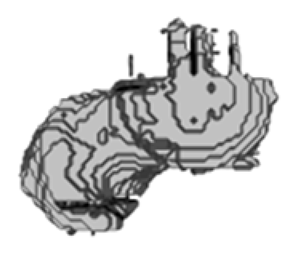

5.2. Comparison and Similarity of 3D Reconstruction Images